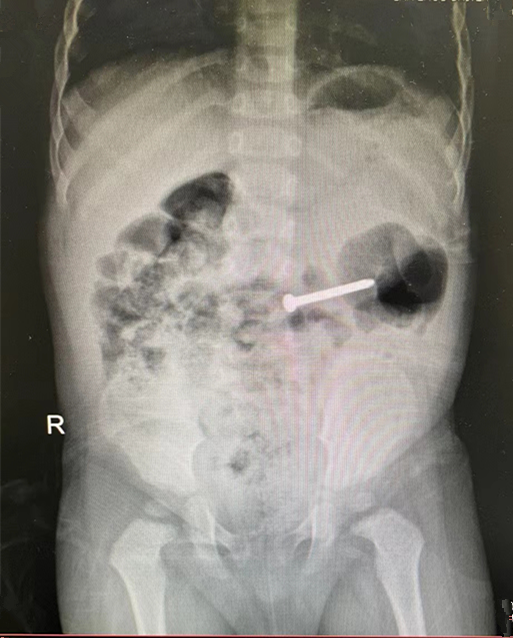

3月11日晚,依旧灯火通明的儿科门急诊内,医护人员正在为不幸患病的孩童实施精心治疗,此时一名母亲急匆匆的抱着一个年仅1岁的孩童前来我院就诊。据家属代诉,患儿于五小时前误吞了一枚铁钉,在当地医院拍片确认后立即赶来我院,接诊医生经相关检查后开据住院证明,并通知小儿消化科值班医生李艳。

患儿收住入院后,李艳第一时间完善了相关检查,并通知科室副主任徐晓楠。接到通知的徐晓楠主任立即从家中赶往医院,在仔细查看患儿检查报告及全面的病情评估讨论后,制定了详细周密的手术计划,拟行内镜下异物取出术。

术中,在麻醉科、内镜中心的密切配合下,可见患儿十二指肠球部可见一枚长约4CM的铁钉嵌顿于肠道,立即予以异物钳夹住钉子并顺利取出,但由于铁钉在患儿体内留存时间较长,其十二指肠嵌顿处黏膜充血水肿、溃疡形成,医护人员有立即给予相关治疗。术后,在医生的精准治疗和护士的精心治疗下,患儿病情日益见好,并于13日上午顺利出院。